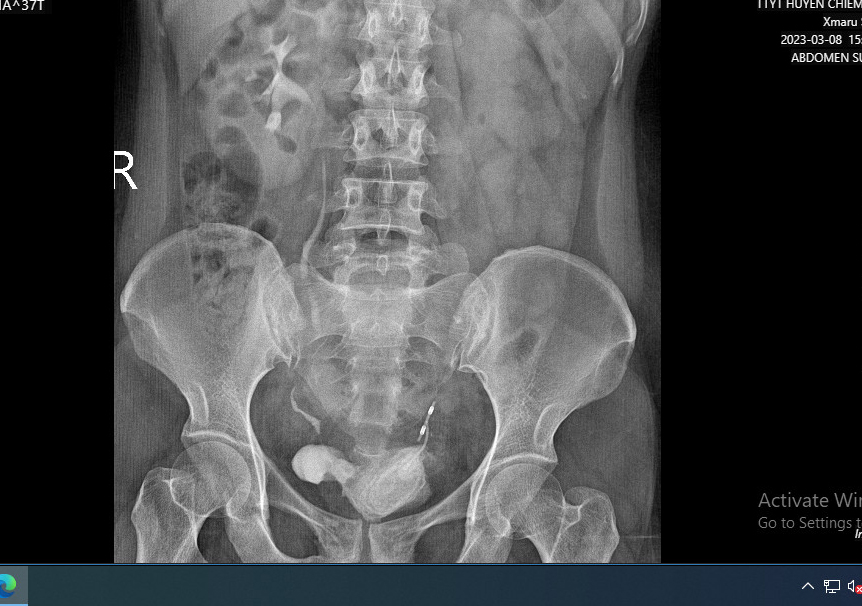

Ngày 08/03, bệnh nhân P.T. H 37 tuổi (xã Phú Bình) đến khám tại TTYT huyện Chiêm Hoá trong tình trạng đau tức vùng bụng dưới, đau sau khi tiểu, ấn hạ vị đau tức. Kết quả chụp Xquang của bệnh nhân cho thấy có sỏi bàng quang và dụng cụ tránh thai vùng tiểu khung, lệch trái. Kết quả chụp cắt lớp vi tính hệ tiết niệu của bệnh nhân cho thấy hình ảnh sỏi bàng quang, sỏi 1/3 dưới niệu quản trái, ứ nước thận trái, TD u mạc treo.

Hình ảnh thể hiện chiếc vòng tránh thai đi lạc trong ổ bụng, bàng quang.